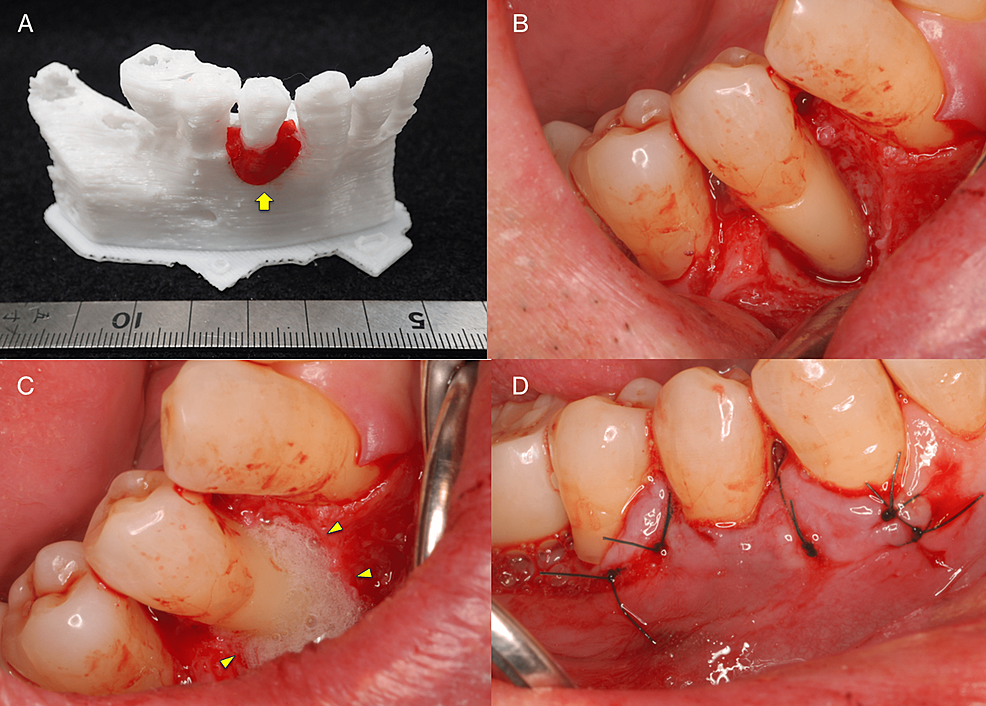

Periodontal tissue regeneration therapy was selected as the surgical procedure to be used considering the maintenance of blood supply from the surrounding tissues as a priority. Prior to surgery, a 3D model was fabricated based on the preoperative CBCT images using a 3D printer.

The fabricated 3D model was then explained to the patient and a simulation was run to confirm the planned use of FGF-2 and the required amount is shown in Figure 3A. Photographs taken during the surgery are shown in Figure 3B–3D. The surgical procedure was performed under local anesthesia (2% lidocaine with 1:100,000 epinephrine). Just one incision was made on the buccal side of the gingival sulcus, and a simplified papilla preservation technique was employed to preserve a wide margin between the mucoperiosteal flaps at the interdental papilla incision [5]. The dissection to reveal the intrabony defect was kept to a minimum to maintain blood flow, with only the buccally attached gingiva being incised. A full-thickness mucoperiosteal flap was then developed. After completion of debridement, a relatively large intrabony defect was observed on the buccal side of #44 spanning the proximal to the distal aspects. Periodontal regenerative medicine (REGROTH®, Kaken Pharmaceutical Co., Ltd., Tokyo, Japan) was applied to the defect, and the flap was closed. It was also injected into the gap during suturing to avoid a decrease in volume due to leakage. After surgery, the patient was instructed to use a mouth rinse containing chlorhexidine (ConCool F®, Weltec Corp., Osaka, Japan) regularly for four weeks. No significant irregularities were observed postoperatively (no excessive swelling, and no suture breakage or infection) and the sutures were removed one week later. After that, the patient was instructed to brush with a soft-bristle toothbrush to prevent damage to the treated area. Brushing using the scrubbing method was started in the second week postoperatively. Meanwhile, the patient continued to receive constant professional care.